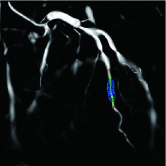

Refer to caption

(a) (a)

(b) (b)

(c) (c1)

(d) (c2)

Figure 8: Results of more precise stenosis detection using the interactive method. (a) Ground truth. (b) Automatic method. (c) Interactive method.

Study of interactive stenosis detection

To prove that the interactive method can do more precise detection than the automatic method, we use the interactive method to detect the stenoses that are not detected by the automatic method. The results are shown in Fig. 8. As can be seen, the interactive method can detect the labeled stenoses that are not detected by the automatic method.